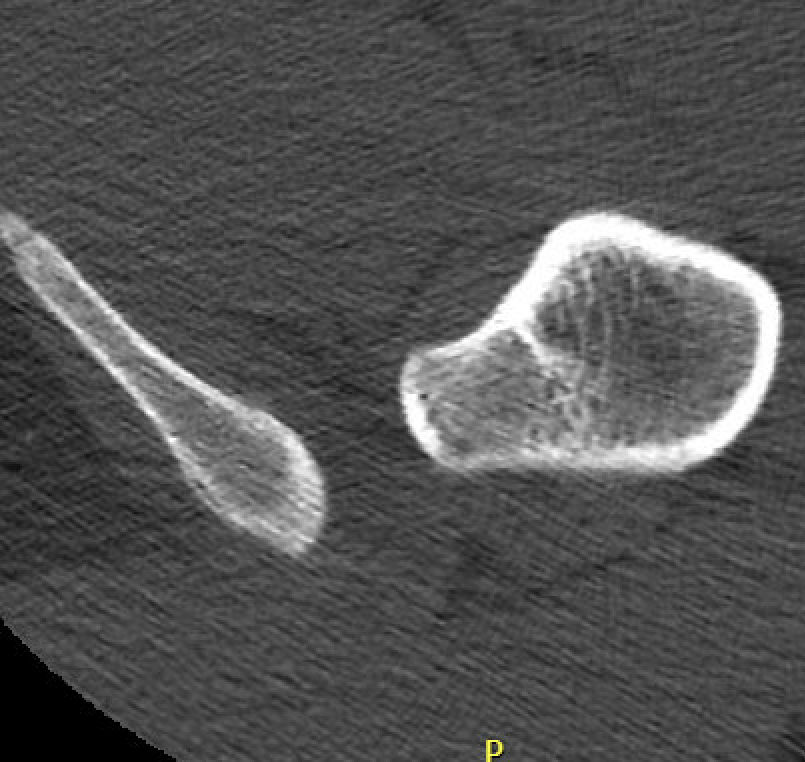

CT

IFI

IFIIFIIFI